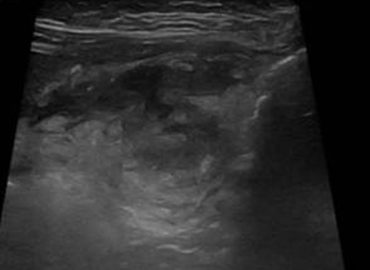

Paciente con masa palpable en mama

Paciente que consulta por Odinofagia, Fiebre y Otalgia. Pérdida de 20 kg en 2 meses.